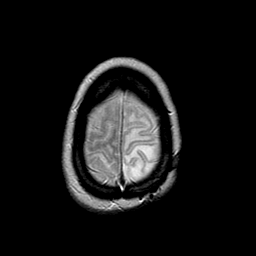

MR Study #2 -- Slice #46

[Home][Help][Clinical][Tour 1][Tour 2][Tour 3] Slice 46